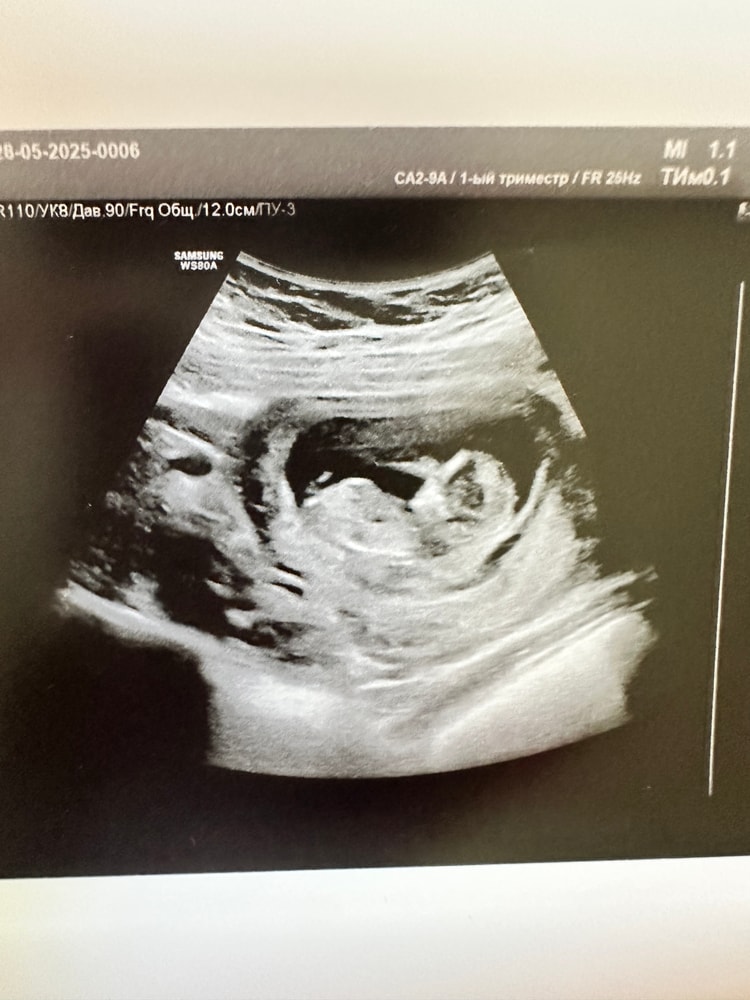

Пол малышаВсем привет! Сегодня была на первом скрининге, срок 12+2, хочу погадать на половом бугорке🤭Видно ли что-то? Вопрос к знатокам в этой области, я профан😀

Fizzy Cherry, на нижнем фото за первой ножкой белая полосочка, конечно фото бы немного другое, но у дочери моей примерно такое же было. А у сыновей сразу под углом достоинство "торчало"))

Сегодня была на УЗИ врач пол смотрела сначала через брюшную стенку: вот половой бугорок, если он смотрит вверх, прям задран, то 85-90% это мальчик, у девочек он более горизонтально сглажен. Потом врач посмотрела ещё трансвагинально и сомнений по поводу пола у нее не осталось